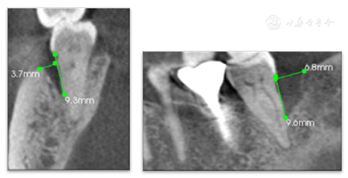

47叩痛(-),不松动,远中及颊侧中央PD7~9 mm,余位点PD3~4 mm,BI2-3,颊侧中央牙龈退缩约2 mm,无附着龈,舌侧牙龈无明显异常(图6,图7)。正中合未及早接触,侧方合未及合干扰,cbct示47颊侧及远中牙槽骨吸收超过根长2/3,颊侧骨缺损深约9 mm,宽约4 mm,远中骨缺损深约10 mm,宽约7 mm(图8,图9)

术后6年,47牙龈无明显红肿,远中及颊侧中央PD 3~4 mm,颊侧退缩根面得到覆盖,颊侧中央出现附着龈,宽约2 mm,BI1,X线片示远中骨缺损明显修复(图25,图26,图27),CBCT示47颊侧骨缺损深约4 mm,宽约1.5 mm,远中骨缺损深约5 mm,宽约3 mm,较初诊时颊侧及远中骨缺损均得到明显修复且骨高度保持稳定(图28,图29)。